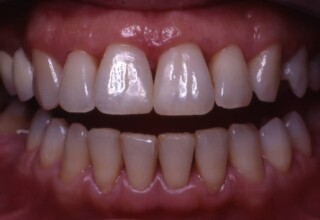

Αποκατάσταση διαστημάτων μεταξύ κεντρικών και πλαγίων τομέων

Τα διαστήματα έχουν δημιουργηθεί κυρίως λόγω των στενών πλαγίων. Μετά την ολοκλήρωση της ορθοδοντικής θεραπείας τα διαστήματα “έκλεισαν” με την τοποθέτηση δύο αποκαταστάσεων σύνθετης ρητίνης.